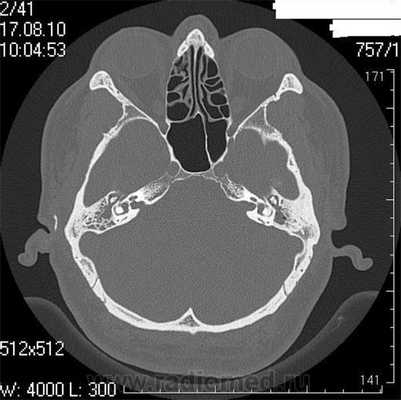

Разрыв цепи слуховых косточек. В анамнезе травма, односторонний характер тугоухости. Возможны изменения барабанной перепонки при отоскопии. На аудиограмме определяется равномерное повышение порогов по воздушной проводимости по всей тон-шкале, с большим костно-воздушным интервалом, при проведении тимпанометрии - тип Ad, отсутствие ипси- и контралатерального акустического рефлекса.

Фиксация молоточка (наковальни). Процесс, как правило, односторонний. На аудиограмме: кондуктивная тугоухость, возможен зубец, подобный зубцу Кархарта, на частоте 0,5 кГц. Тимпанограмма с наличием on/off-эффекта (в момент начала «включения» рефлекса имеется узкий пик). При проведении СКТ височных костей возможна дислокация молоточка и визуализация оссифицированной наружной связки (что является наиболее частой причиной фиксации).

Врожденные пороки развития среднего уха. Односторонний процесс, развивается с раннего детства. При осмотре часто встречается патология ушной раковины или изменения слухового прохода. На аудиограмме: кондуктивная тугоухость без сенсоневрального компонента. Тимпанограмма: тип А или Ad, ипси- и контралатеральный акустический рефлекс отсутствует. При проведении СКТ выявляются поражения костных структур барабанной полости в виде дисплазии или аплазии слуховых косточек, дистопии канала лицевого нерва, костные изменения в области окон лабиринта.